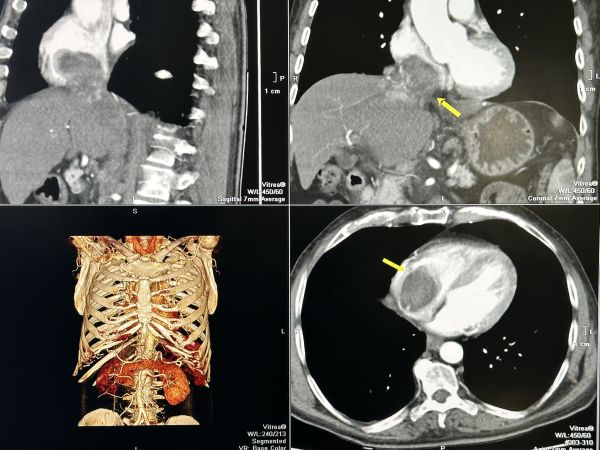

Туморът с размери 7 на 9 см. е ангажирал и изпълнил почти изцяло кухината на дясното предсърдие на сърцето и е застрашавал да запуши белодробните артерии и белия дроб.

След постъпването на пациента в лечебното заведение е направен скенер, от който се установяват злокачествените образувания в кухините на сърцето и наличието на две огромни туморни огнища в черния дроб.

Туморът се разпространява и в коремната област, като обхваща и запушва прехода на долна празна вена, преминаваща през черния дроб. Размерът на туморното образувание в този участък е с дължина 17 см и широчина 3 см.